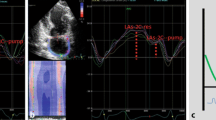

Speckle tracking echocardiography of the LA is a relatively new echocardiographic method. With dedicated software an unique pattern of speckles is identified within the LA wall and these speckles are tracked on frame-by-frame base throughout the cardiac cycle. The measured change in distance between the different speckles is used to calculate LA deformation. LA reservoir strain is a prognostic biomarker, which has been evaluated for patients with HF. Commercially available software (QLAB 13, Philips Healthcare, Eindhoven, the Netherlands) was used to measure LASr on non-foreshortened apical four- and two-chamber views of the LA with a frame rate of 60–80 frames per seconds. The LA endocardial border was automatically drawn followed by manual adjustment if required. The reference point for LA strain analysis was taken at the onset of the QRS-complex (R-R gating) (Fig. 1) [12].